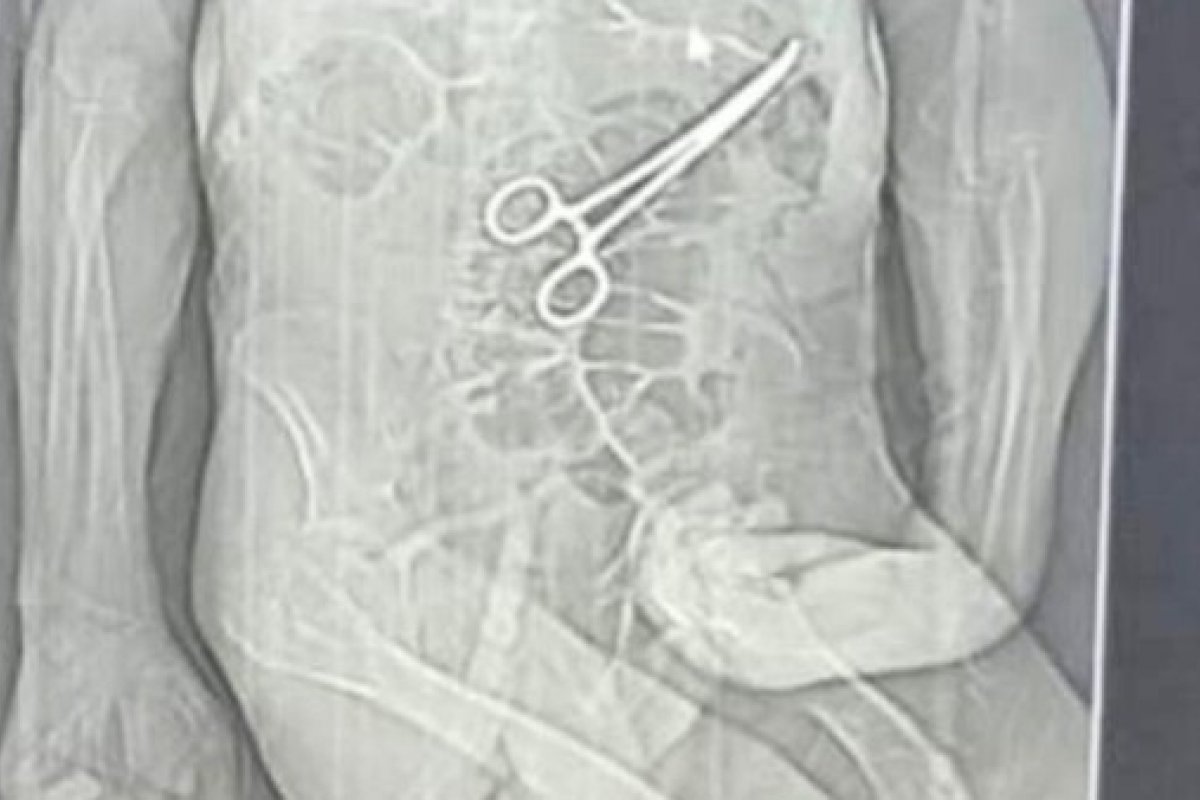

Foto: Rádio Nova FM/Reprodução

A família de um aposentado que morreu na véspera do último Natal em João Pinheiro, no noroeste de Minas Gerais, acusa médicos do hospital municipal de esquecerem uma pinça no abdômen do idoso durante uma cirurgia feita semanas antes do óbito.

Após a cirurgia, o paciente voltou a apresentar sintomas graves, o que levou à realização de novos exames. Nesse momento, uma tomografia identificou, segundo a secretaria, "um corpo estranho na cavidade abdominal".

Os parentes também afirmam que só souberam do que de fato havia ocorrido por meio de uma reportagem de uma rádio local, quando tomaram conhecimento da imagem de uma tomografia indicando uma pinça no abdômen de Manoel.